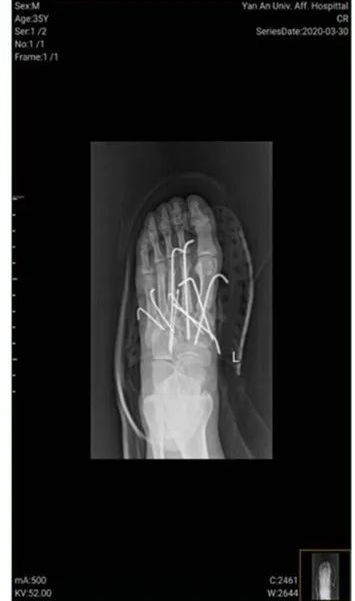

术前 CT 骨折脱位,并有大量石块

清创术后,骨折脱位复位良好